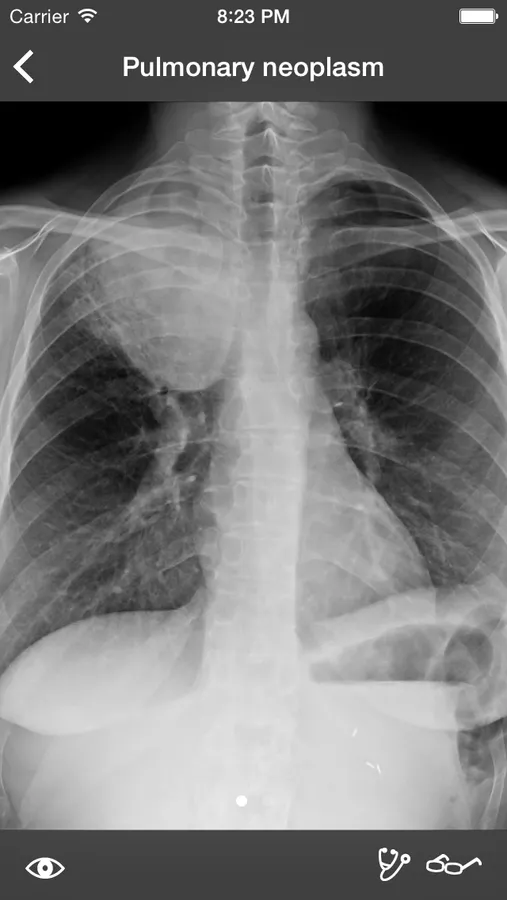

RealWorld Radiology is your ultimate guide to the basics of thoracic imaging. Learn to read chest X-rays in no time and discover the most frequent diagnoses through multiple fully annotated examples.

- High-resolution X-rays

- Drawings of every radiological finding right on the X-ray

Our cases have been especially selected for their high pedagogical value and real-world representativeness. They can be classified either by diagnosis (e.g. pneumonia, atelectasis, pulmonary fibrosis) or by actual radiological finding (e.g. alveolar opacities, interstitial opacities, silhouette sign), making the learning of the differential diagnosis easier than ever while keeping each case easy to find for quick access.